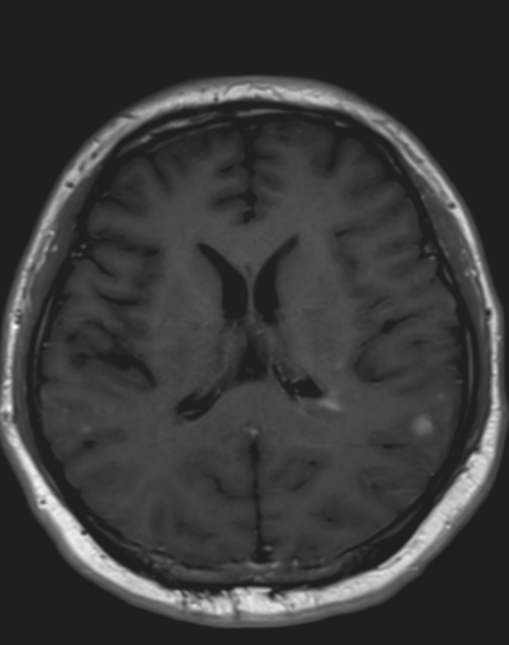

医生要求紧急做颅脑MRI,影像很快就传到了电脑上(图1-6)。医生解释,小脑蚓部占位考虑“脂肪瘤”,另有侧脑室旁白质脱髓鞘和左侧额顶叶皮质性脑炎的改变,“癫痫”可能为“继发性癫痫”。

图4 侧脑室旁病变T1WI`